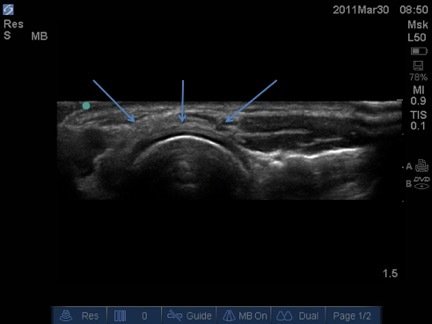

Lateral Elbow Short Axis Image

Arrows: Common Extensor Tendon